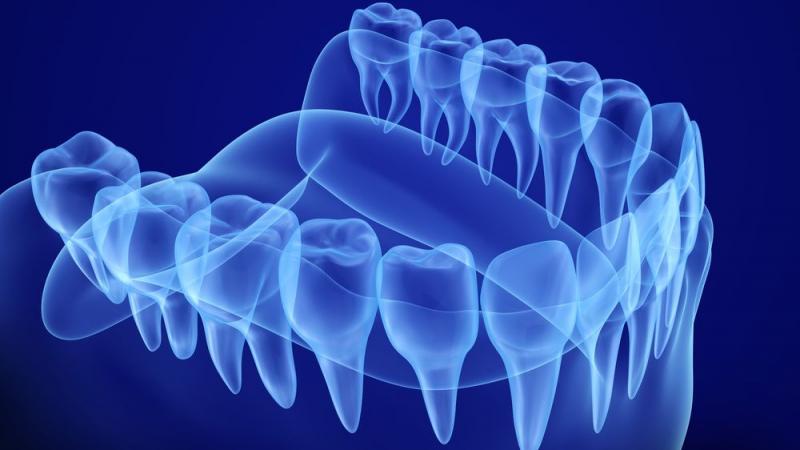

Diş hekimliği uygulamalarında 1990’lı yıllarda başlayan dijitalleşme elbette yalnızca robotlardan ibaret değil. Hem teşhisin doğruluğunu hem de hastanın diş hekimi koltuğundaki konforunu artıran ve ciddi ölçüde zaman tasarrufu sağlayan dijital diş hekimliği uygulamalarında “ağız içinden 3 boyutlu görüntü alınması” kilit noktayı oluşturuyor. Bu uygulamanın getirdiği en büyük özelliklerden biri hastanın ağzına, öğürme ya da bulantı refleksi gibi sorunlara yol açan kalıp hamurlarını yerleştirme zorunluluğunu ortadan kaldırması. Hata oranını minimuma indiren bu modelleme sayesinde ayrıca daha önce günler süren yeni implant, protez ya da dolgular daha hasta diş hekimi koltuğundan kalkmadan üretilebiliyor, üstelik hastanın tedavisi de hızla yapılarak implant veya dolgu hemen yerleştirilebiliyor.

Klasik diş hekimliği uygulamalarında hastanın sorununa tam olarak teşhis konulması ve tedavi ihtiyaçlarının belirlenmesi en az birkaç seans alırken hekime çok geniş bir hareket yetisi kazandıran 3 boyutlu görüntüleme sayesinde hastanın şikayetine daha ilk seansta büyük oranda teşhis konulabiliyor, üstelik tedavi protokolü de belirleniyor. “Böylece hasta hem röntgenden ve tomografiden daha az şuaya maruz kalıyor hem de daha tedaviye başlamadan tüm planımızı ve yol haritamızı kendisine aktarabiliyoruz. Örneğin implant gerekiyorsa hangi çapta, hangi uzunlukta implant koyacağımızı kendisiyle paylaşıyor ve böylece bir sürprizle karşılaşmıyoruz” diyen Diş Hekimi Hatice Ağan, bu yöntem sayesinde daha az sarf maddesi kullanarak daha az atık ürettiklerini, böylece doğaya etkilerinin de çok daha az olduğunu vurguluyor.

Dijital teşhis imkanı ağız diş sağlığıyla ilgili neredeyse tüm sorunların tespitinde artık mümkün hale gelmiş durumda. Tek bir tedavi protokolü değil hastanın ihtiyacına özel tedavileri mümkün kılan bu uygulamalar mevcut sağlıklı dişlerdeki kayıpları da en aza indiriyor. Örneğin ağız içinde eksik bir diş varsa ve bu bölgeye protez yapılması söz konusuysa artık yandaki dişlerin kesilmesine ve onların da ömrünün azaltılmasına gerek olmadan implantlardan faydalanarak, 3 boyutlu görüntüleme sayesinde eksik boşluğun genişliğine uygun kişiye özel implant dayanakları ve protezler yapılıyor.